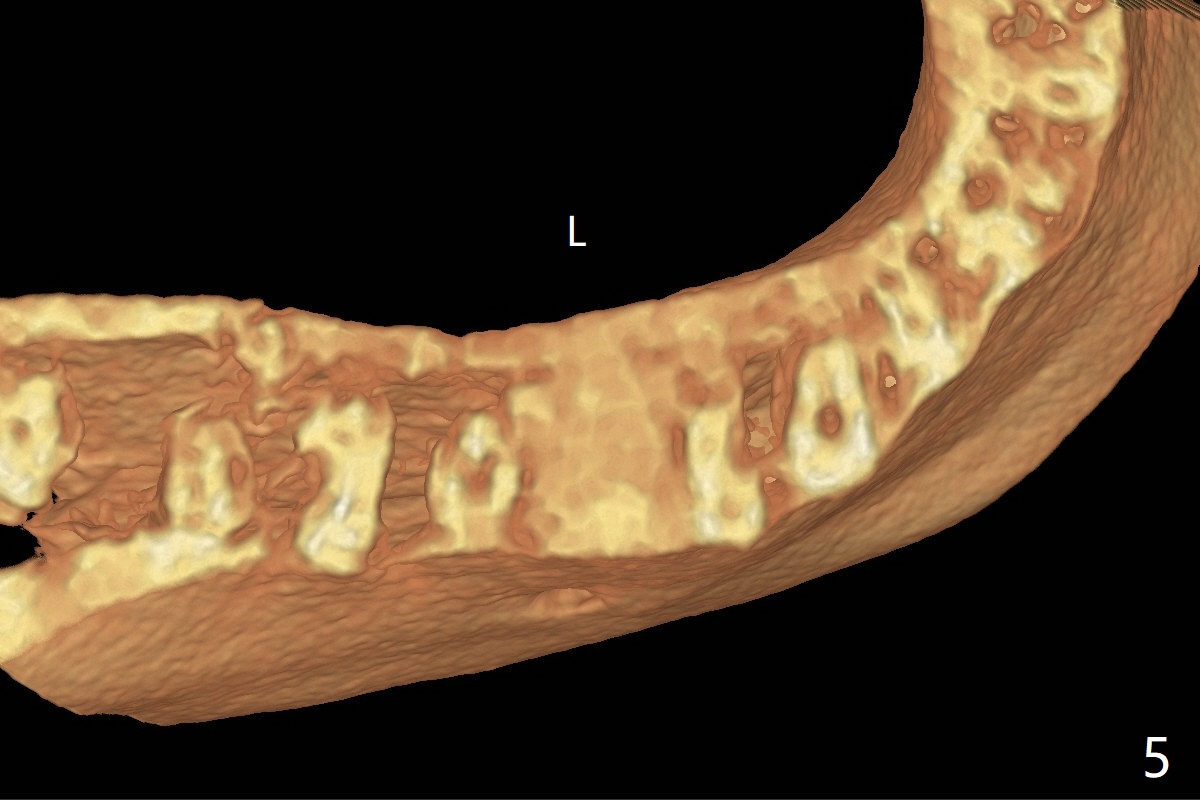

CT is taken 4 months post panoramic X-ray (Fig.2).  C: coronal; S: sagittal; A: axial; B: buccal.  Coronal (Fig.6) and sagittal (Fig.7) sections.  It seems that the lesion does not invade the thin buccal plate or the periodontium.